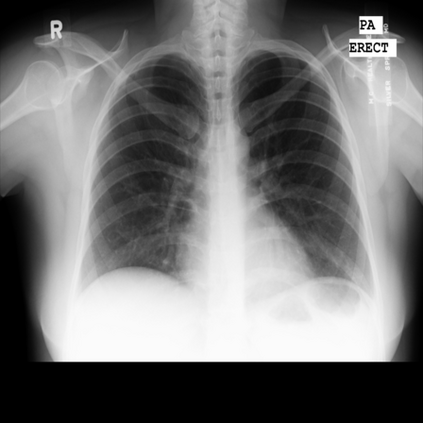

The integration of deep learning systems into healthcare has been hindered by the resource-intensive process of data annotation and the inability of these systems to generalize to different data distributions. Foundation models, which are models pre-trained on large datasets, have emerged as a solution to reduce reliance on annotated data and enhance model generalizability and robustness. DINOv2 is an open-source foundation model pre-trained with self-supervised learning on 142 million curated natural images that exhibits promising capabilities across various vision tasks. Nevertheless, a critical question remains unanswered regarding DINOv2's adaptability to radiological imaging, and whether its features are sufficiently general to benefit radiology image analysis. Therefore, this study comprehensively evaluates DINOv2 for radiology, conducting over 100 experiments across diverse modalities (X-ray, CT, and MRI). To measure the effectiveness and generalizability of DINOv2's feature representations, we analyze the model across medical image analysis tasks including disease classification and organ segmentation on both 2D and 3D images, and under different settings like kNN, few-shot learning, linear-probing, end-to-end fine-tuning, and parameter-efficient fine-tuning. Comparative analyses with established supervised, self-supervised, and weakly-supervised models reveal DINOv2's superior performance and cross-task generalizability. The findings contribute insights to potential avenues for optimizing pre-training strategies for medical imaging and enhancing the broader understanding of DINOv2's role in bridging the gap between natural and radiological image analysis. Our code is available at https://github.com/MohammedSB/DINOv2ForRadiology